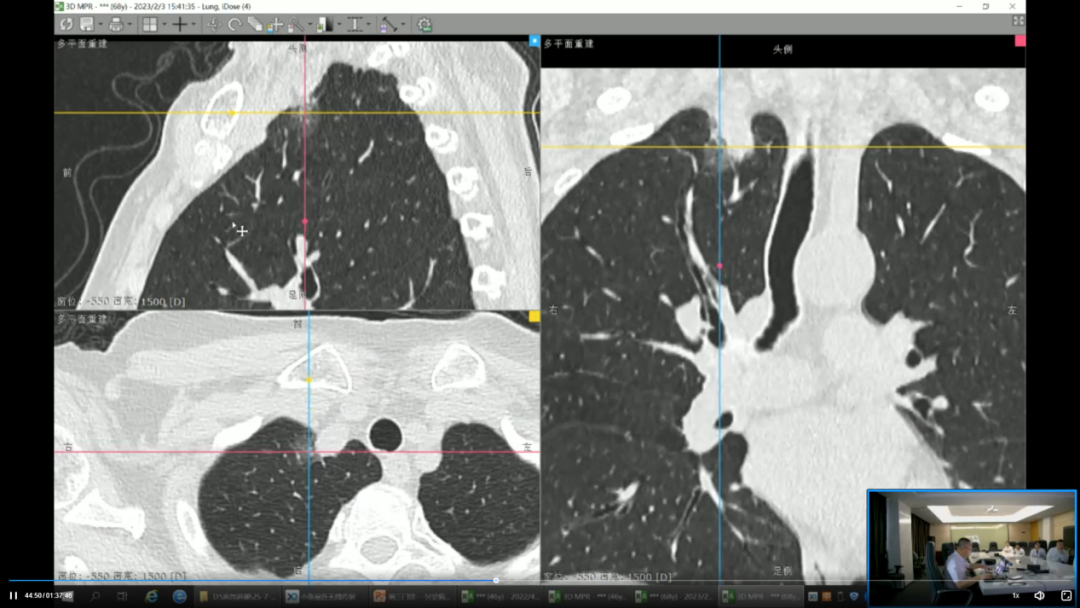

AI 与影像技术创新: 集团积极布局人工智能与前沿影像技术,以智能化、精准化驱动诊断产品升级。在 AI 智能诊断领域,陆续推出 CT 骨密度智能分析、CT 冠脉钙化积分评估、CT-FFR(无创血流储备分数)分析等多款 AI 辅助诊断产品,提升诊断效率与一致性。在影像检查技术方面,成功推出并应用了磁共振全身成像(MMR)、普美显动态增强磁共振(DCE-MRI)肝癌早筛、脑认知功能 AI 辅助解读、心脏全面磁共振检查(CMR)以及儿童生长发育综合评估等一系列前沿检查与评估方案,显著拓展了疾病的早期发现与精准评估能力。